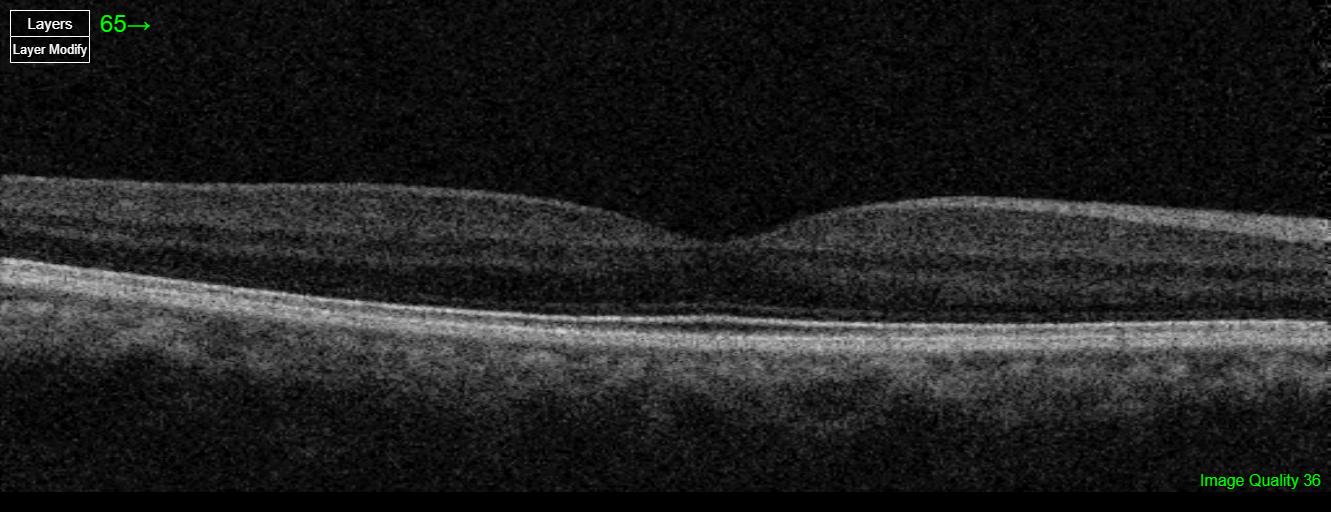

Care1 Retina Surgeon’s Clinical Insight

This patient has pachychoroid syndrome and old central serous retinopathy in the left eye. Fundus photography reveals pachydrusen, and OCT imaging shows a thickened choroid. In the left eye, there is a small pigment epithelial detachment (PED) without any associated subretinal fluid. A prominent choroidal vessel is noted beneath the PED, consistent with pachychoroid features. Steroid medications, including topical, nasal, or inhaled forms, should be avoided unless absolutely necessary. No other lifestyle modifications are recommended. Continued observation and follow-up are appropriate, and the Care1 ophthalmologist will remain available to assist with ongoing management.